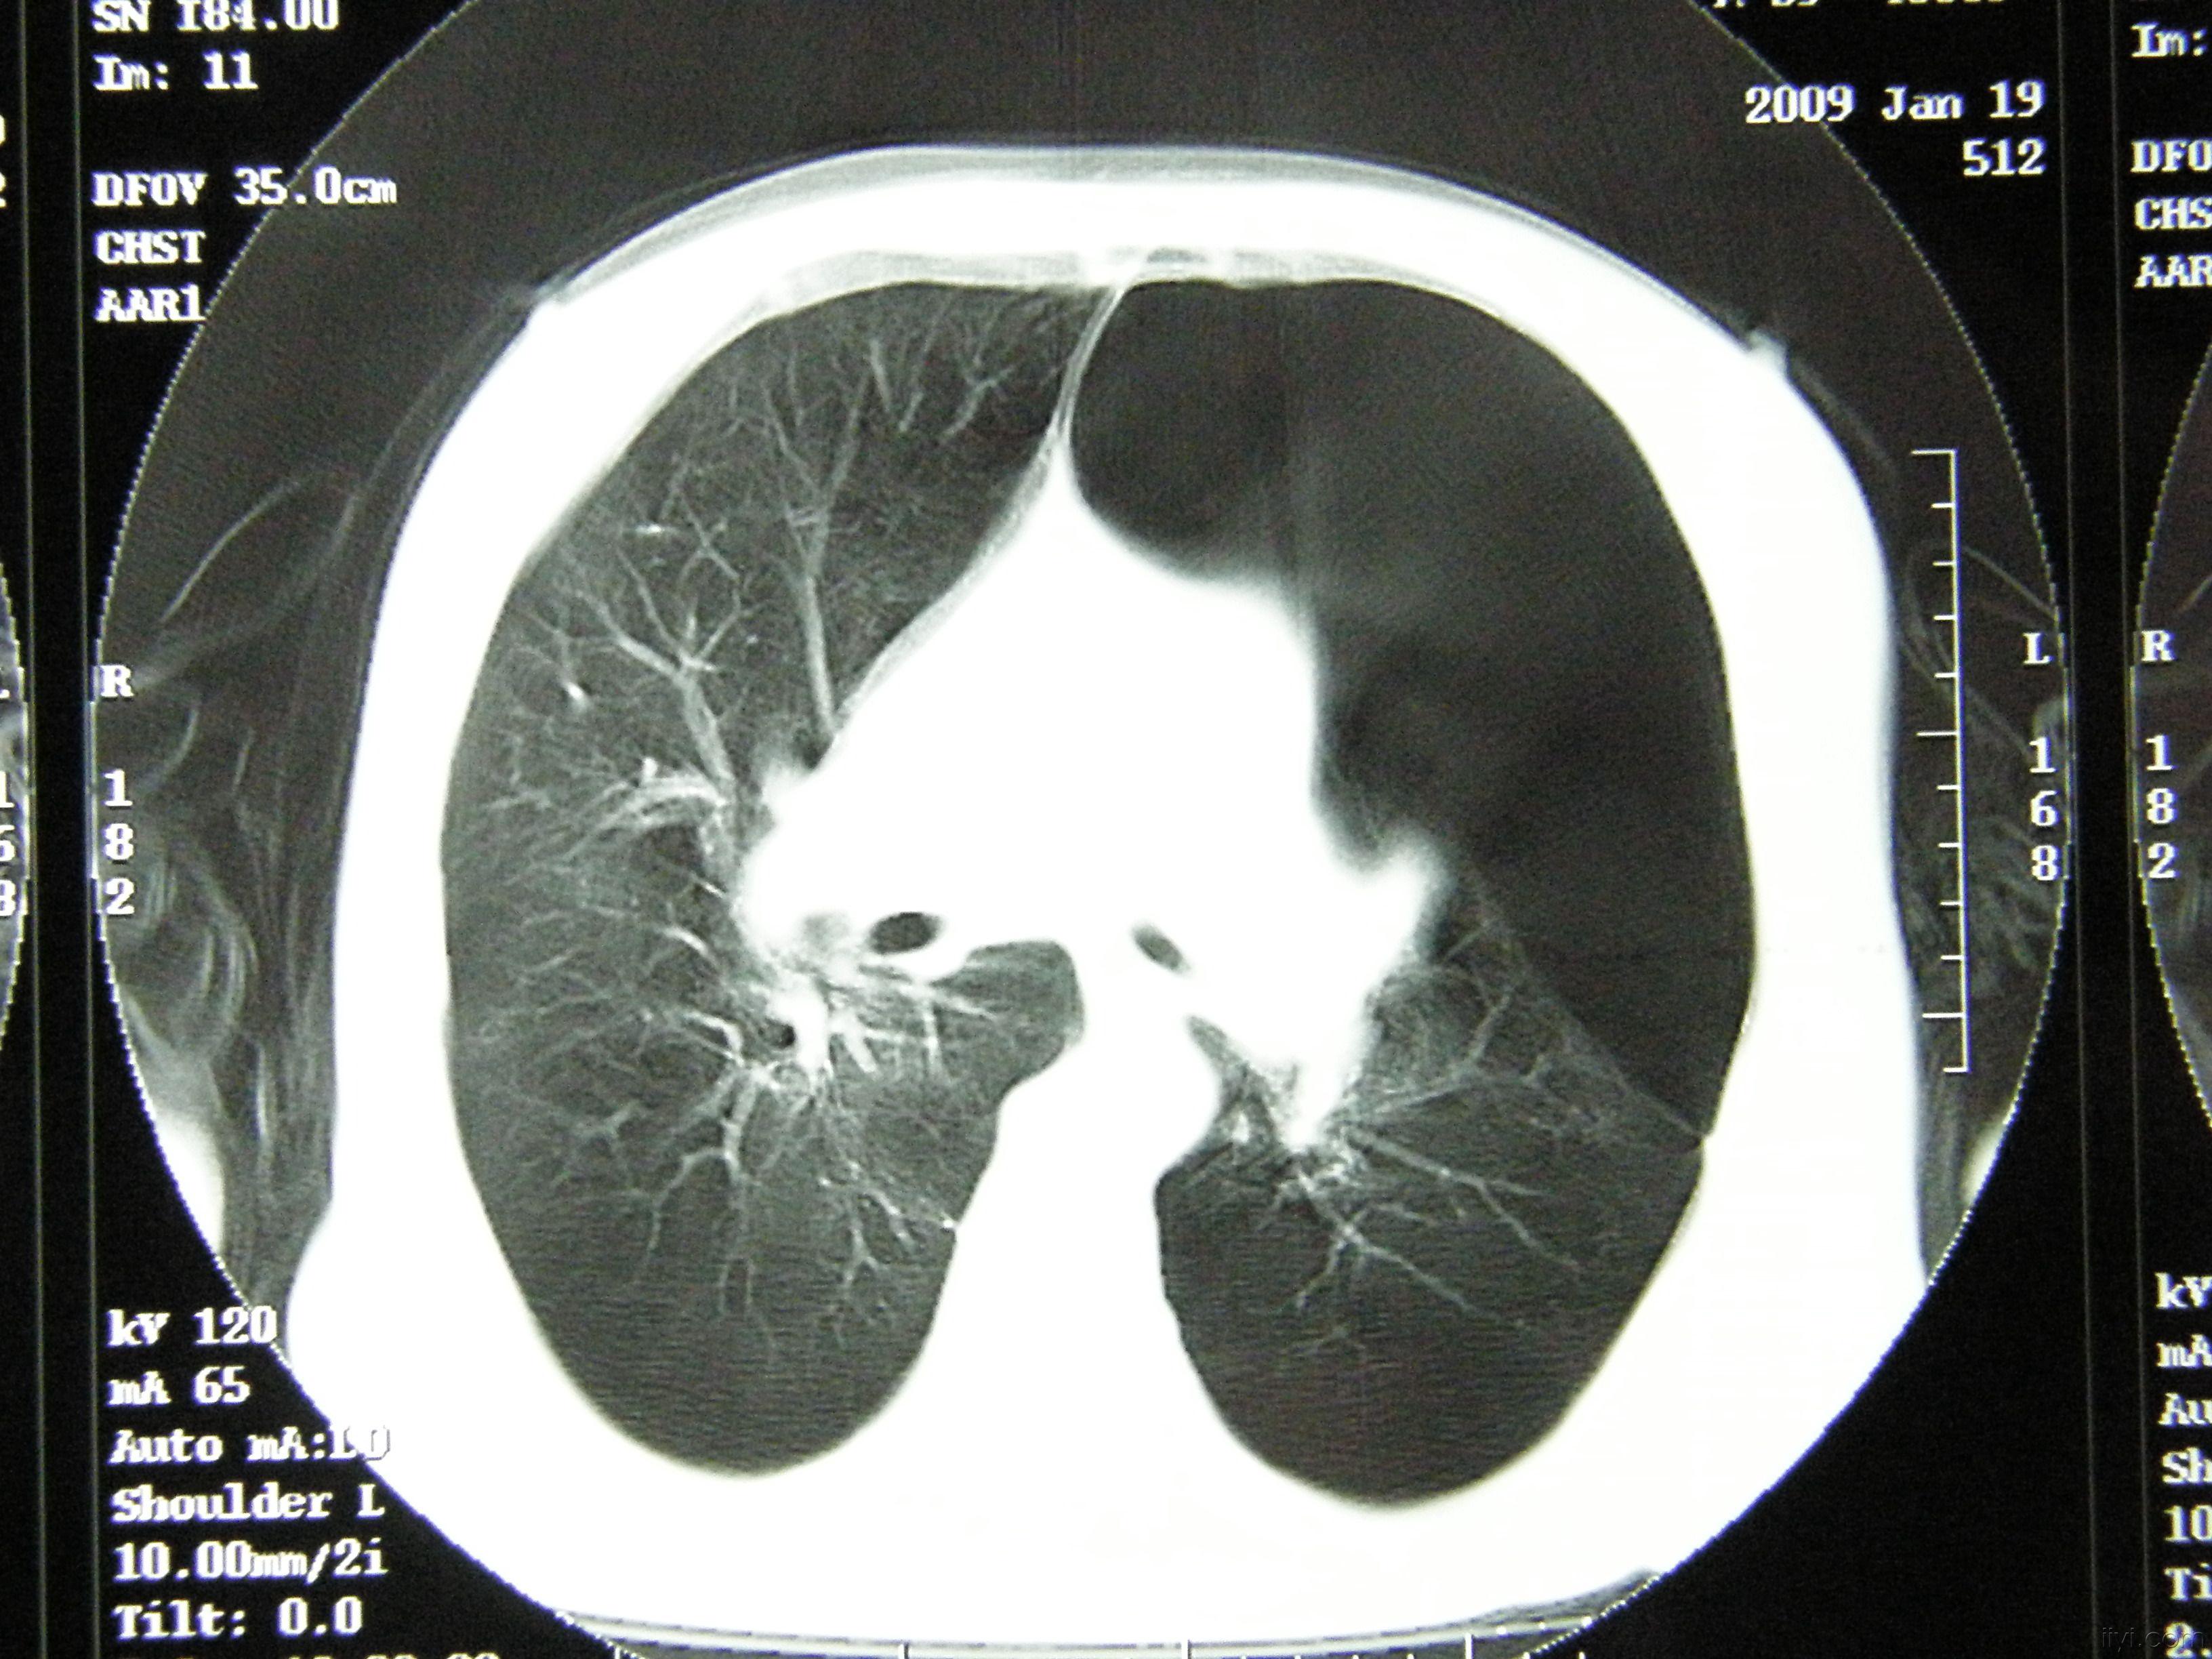

是气胸还是肺大疱

胸部ct 薄层ct可以发现肺大泡,另外一些隐匿部位的 气胸,胸片不能

巨大肺大泡误诊为气胸一例

肺气肿,气胸,肺大泡